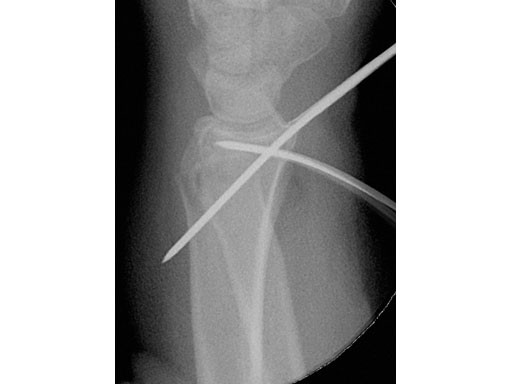

A young woman, 1,5 m tall, 45 kg, sustained a very distal C1.1 fracture of the distal radius.

Fig 1 Intraoperative view showing reposition of the radiocarpal joint with the K-wire.